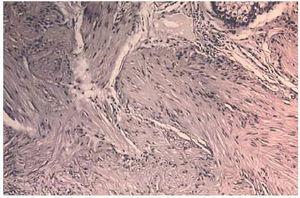

Un varón de 70 años de edad, sin antecedentes patológicos de interés, consultó por presentar lesiones cutáneas en hemicara y costado izquierdo desde los 25 años de edad. Inicialmente estas lesiones eran asintomáticas, pero actualmente se acompañaban de un intenso dolor durante los meses de invierno, con el mínimo roce, y también de forma muy llamativa presentaba crisis de dolor paroxístico durante el sueño, especialmente si éste se acompañaba de pesadillas, ocasionándole constantes despertares nocturnos. La exploración física reveló una placa compuesta por lesiones papulonodulares de color eritematovioláceo, dolorosa a la palpación y de consistencia firme, localizada en la región mandibular izquierda (fig. 1). Se observaron también numerosas lesiones papulosas de diámetro inferior a 1 cm, unas de coloración marrón claro y otras de color de la piel adyacente, con superficie lisa y bien circunscritas, localizadas en brazo y en costado izquierdo, afectando tanto a su cara anterior como posterior, donde varias de estas lesiones se agrupaban siguiendo una disposición segmentaria. Al interrogatorio realizado el paciente refería varios miembros de su familia afectados con las mismas lesiones, en concreto su abuelo paterno, su padre y una hermana, en la que coexistían además leiomiomas uterinos. Se confirmó el diagnóstico de leiomiomas cutáneos múltiples unilaterales familiares mediante exéresis-biopsia de una de las lesiones (fig. 2). Los estudios complementarios realizados (analítica completa de sangre y orina, proteinograma y radiografía de tórax) no detectaron anomalías. Dada la intensa sintomatología que presentaba el paciente, y la limitación del tratamiento quirúrgico para extirpar todas las lesiones dolorosas, se decidió realizar tratamiento médico con gabapentina. Las dosis iniciales fueron de 300 mg al día, ascendiendo progresivamente hasta alcanzar la dosis diaria de 900 mg. A las 2 semanas del iniciarse el tratamiento el paciente refería una importante disminución del dolor, de las molestias subjetivas que le ocasionaban las lesiones e incluso una disminución del tamaño de las mismas que no fue comprobado clínicamente. El paciente no presentó efectos secundarios y actualmente está con dosis de mantenimiento de 900 mg/día, realizando controles periódicos sin recidiva de su sintomatología.

Fig. 2.--Detalle histopatológico de la dermis profunda, donde se aprecia una neoformación circunscrita compuesta por fibras musculares lisas entremezcladas con el colágeno circundante. (Hema-toxilina-eosina, ×80.)